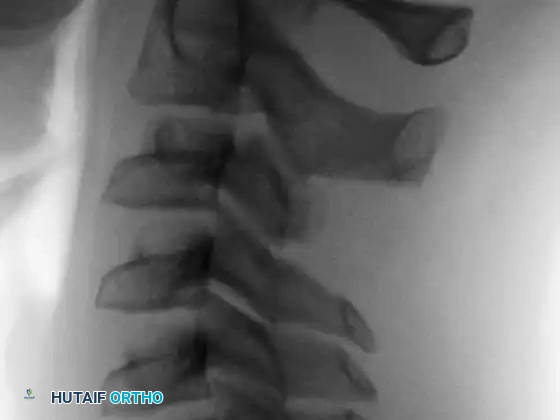

Anteroposterior and lateral radiographs of the cervical spine in a 10-year-old boy presenting with a 1-month history of severe neck pain, demonstrating a distinct lesion of the C3 spinous process.